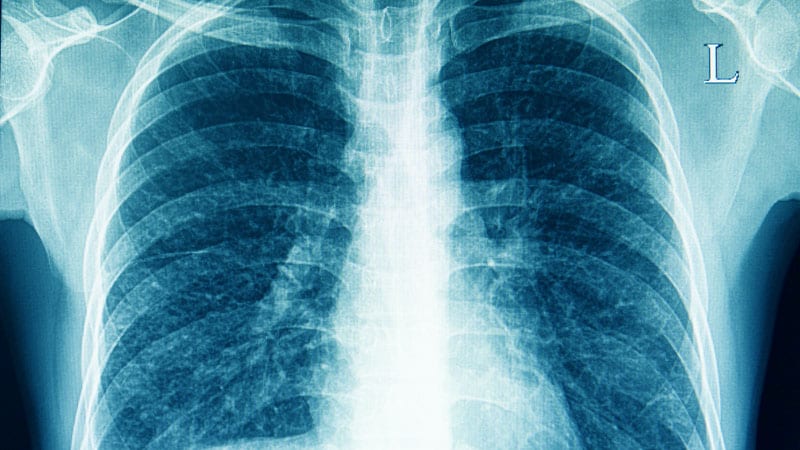

Нормальная рентгенограмма легких: что нужно знать

Раздел: Мудрость в объективе